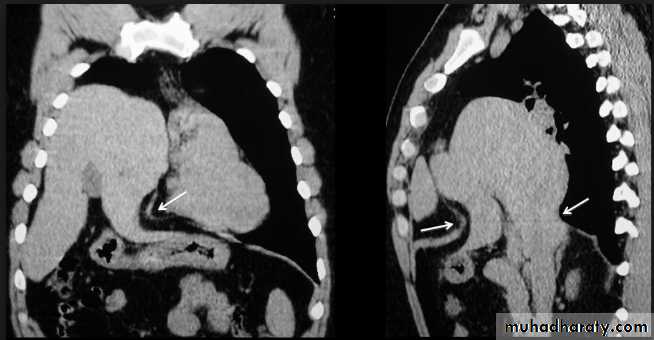

It is important to know the extent of aortic dissections because those involving the ascending aorta are treated surgically, while those confined to the descending aorta are usually treated by an endovascular approach if conservative management is not appropriate.

Aortic dissections can be shown with CT (and MRI) and these non-invasive techniques have, in practice, replaced aortography.

Aortic dissection